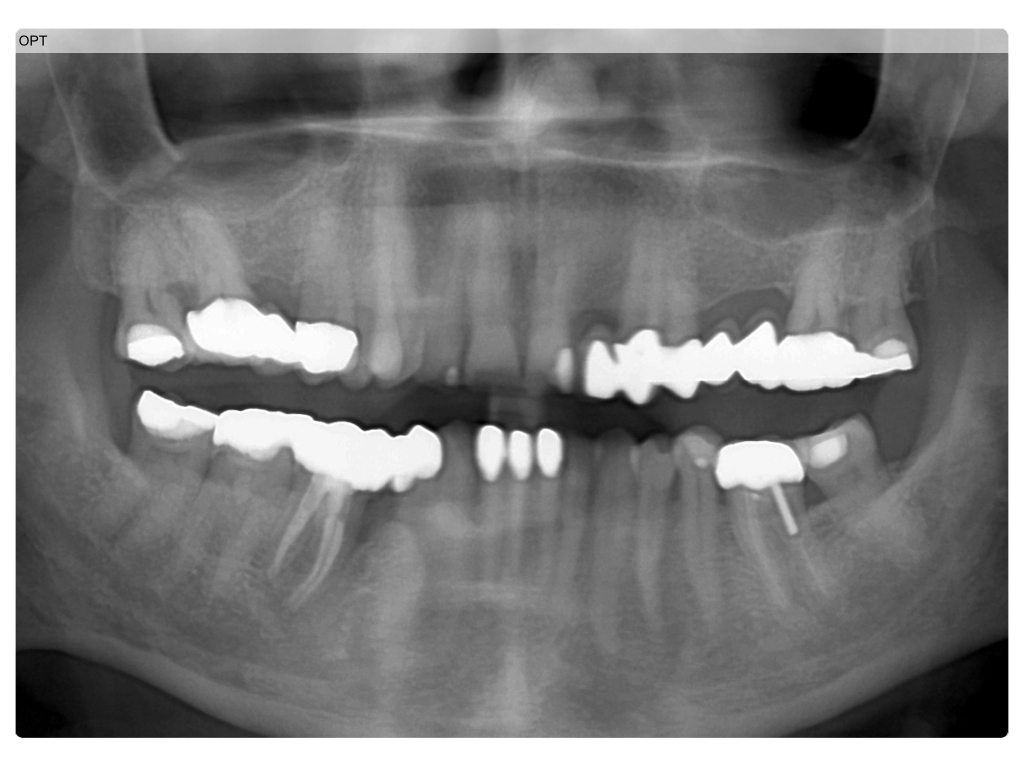

Zahnerhalt mit allen Mitteln?